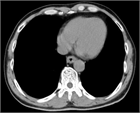

1. 急性期の病状把握のためCT、上部消化管内視鏡検査は必要である(推奨度2)